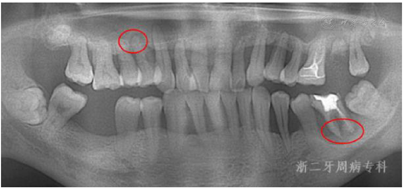

2018年12月、2019年1月:牙周基础治疗后10年复诊。患者口腔卫生维护一般,口内可见少量龈上结石形成,部分牙龈充血肿胀,牙周探诊出血位点明显增多,牙周袋较2013年情况严重。牙周维护后,牙龈肿胀减轻,部分位点龈缘仍充血红肿(图18)。全口曲面体层X片示:与2011年4月比较,24近中牙槽骨再次出现角形吸收,36近中根牙槽骨进一步吸收;而全口其余位点牙槽骨没有明显出现进一步吸收现象,基本维持原有高度,37、46缺牙区牙槽骨高度无明显降低(图19)。PD 4~6 mm的位点数为85个,≥7 mm位点有7个,其中36舌侧远中牙周袋更是深达12 mm,全口BOP(+)%:26.8%(图20)。

2021年8月:牙周基础治疗后13年复诊,患者口腔卫生维护佳,牙周状况较上一次复诊牙龈色粉,无明显红肿,口内下前牙区可见少量龈上结石(图23),松动度进一步改善,全口BOP(+)%进一步下降至15.4%,但36仍可探及较深牙周袋,近中探诊能触及根尖(图24)。X线片示:与2018年12月比较,36近中根牙槽骨进一步吸收,吸收已达根尖,而全口其余位点牙槽骨没有明显出现进一步吸收现象;14根尖可见低密度影(图25)。口腔锥形束CT(CBCT)示:36近中根牙槽骨吸收至根尖,牙齿与骨面基本分离,舌侧骨壁缺失,颊侧骨壁较低(图26)。本次行复发危险评估结果示高复发危险度,但与上次评估相比,由3个高度危险因素转变成2个高度与1个中度,情况有所好转(图27)。

牙周基础治疗是治疗牙周炎最基本也是最有效的手段,是任何牙周病患者治疗成功的关键[2]。本例患者发生重度牙周炎的主要原因为口腔卫生差,菌斑控制不佳,早期出现刷牙出血等牙周炎早期症状时未予重视。初诊时患者全口牙齿松动,牙龈炎症严重,仅经过彻底的牙周基础治疗,包括口腔卫生指导、龈上洁治、龈下刮治与根面平整等,去除菌斑和牙石等局部刺激因素,配合牙周固定,使牙齿松动度改善,牙周袋深度明显降低,有效控制了牙龈组织炎症,同时出现牙槽骨修复。随访13年来,除早期拔除的37、46外,绝大多数Ⅱ~Ⅲ度松动、牙槽骨吸收至近根尖、愈后无望的患牙得以长期保留,功能恢复良好。46对应位点牙槽骨部分修复再生(图28)。患者13年来探诊深度水平随着基础治疗及维护治疗的进行不断改善,目前基本维持稳定(图29)。